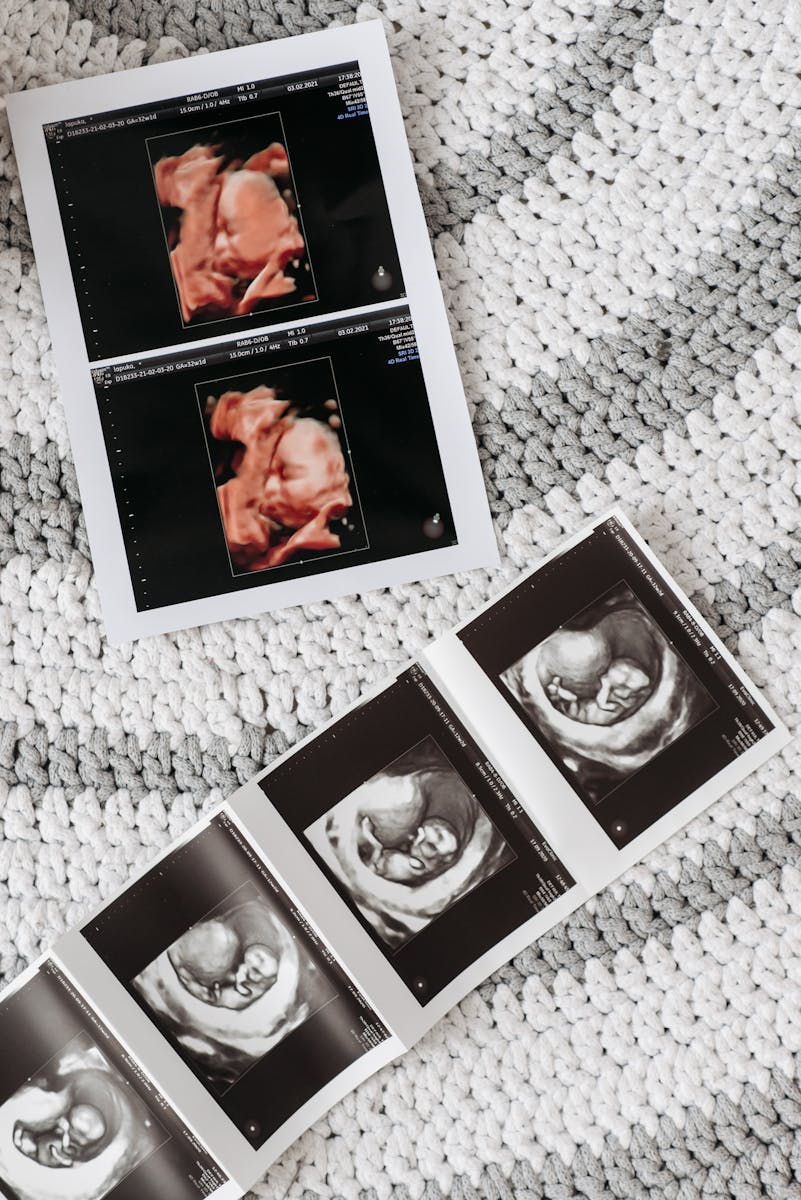

That final biomedical challenge will be my primary focus here. On the reproductive side, it includes artificial contraception, surrogacy, and in vitro fertilization (IVF), as well as egg freezing, genetic editing in the womb, genetic screening of fertilized embryos, and artificial wombs.